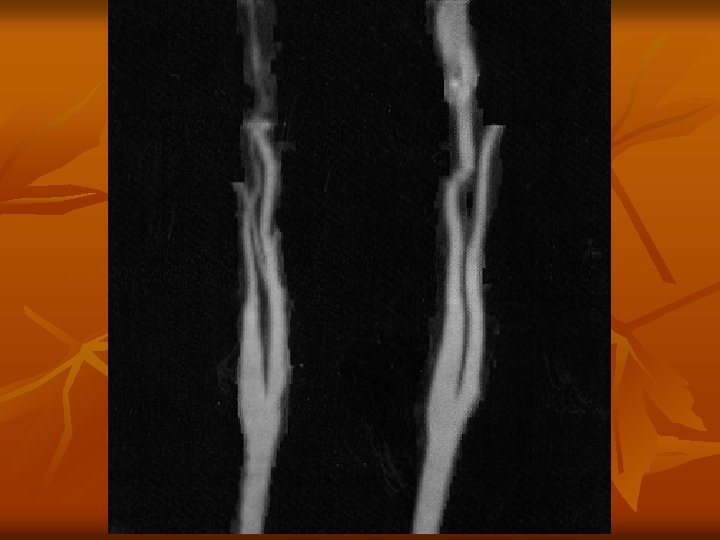

A CTA leggyakoribb alkalmazása n n n Renovascularis és cerebralis vasculatura obliterativ folyamatának meghatározása Abdominalis és thoracalis daganatok műtéti eltávolítása előtt vasculatura ábrázolása Pulmonalis embolia gyanújának esetén! Első vizsgálati lépésként!

CTA vizsgálat hátrányai n n n Rtg sugár alkalmazása Stacioner képalkotás, nem dynamicus Limitált térbeli felbontás - kiserek Artefactumok(csontstruktúra) Kontrasztanyag alkalmazása szükséges Kontraindicatiok: kontrasztanyag érzékenység cardiorespiratoricus állapot renalis állapot